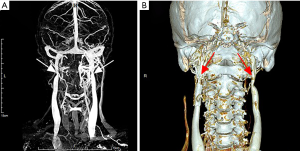

Among the 27 cases, only one patient underwent surgical intervention. This 49-year-old male, who complained of intermittent headaches, persistent head noises and tinnitus for 3 years, was confirmed the diagnosed as severe bilateral IJVS surrounded by abnormally distorted vertebral venous plexuses by CE-MRV in Xuanwu Hospital in November 2017. 3D reconstruction CT maps showed the bilateral IJVS at J3 segments were obviously compressed by the adjacent lateral mass of C1 and styloid process. The styloid processes length was 4.4 cm in left and 4.1 cm in right (Figure 1). The patient underwent bone resection and balloon dilation in left IJV after finished his comprehensively preoperative assessment, as the outflow disorder in left IJV was more severe than that in right. Both the styloid process and the lateral mass of C1 on the left side were resected and the left stenotic IJV was corrected by balloon dilation. The symptoms were relieved immediately after surgery. More importantly, at one-year follow-up post-operation, all symptoms were disappeared and the previous left stenotic IJV had restored normal blood flow and the abnormally tortuous vertebral venous plexus was also decreased in his follow-up CTV maps (Figure 2).